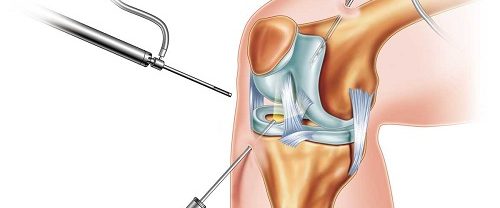

Artroskopik Menisküs Onarımı Nedir? Artroskopik menisküs onarımı, diz eklemindeki menisküs adı verilen kıkırdak dokusunun, minimal invaziv bir cerrahi prosedür olan artroskopi yöntemiyle onarılması işlemidir. Menisküs, diz eklemleri içinde bulunan C şekilli kıkırdak yapıdır ve ek yüzeylerin düzenli bir şekilde yük görünümünü sağlar. Ancak travma, aşırı zorlanma veya yaşlanmaya bağlı olarak menisküs yırtılabilir. Artroskopik menisküs onarımı,…

Menisküs Yaralanmaları ve Onarımı Kelebek Tekniği ile Menisküs Onarımı | Menisküsler, diz ekleminde bulunan kıkırdak yapılar olarak bilinir. Bu yapılar, dizin stabilitesini sağlamak ve darbe emici bir yastık görevi görmektedir. Ancak, spor aktiviteleri, ani dönüşler, yüksek darbe alımı gibi durumlar menisküs yaralanmalarına yol açabilir. İşte menisküs yaralanmaları ve onarımı hakkında daha detaylı bir bakış: Menisküs…

Diz Artroskopisi Nedir? Diz artroskopisi, diz bölümlerinin iç bölümünün küçük bir kamera (artroskop) ile girilerek yapılan cerrahi bir işlemdir. Bu işlem, iç dizinin daha ayrıntılı ve tedavisi için kullanılır. Artroskop, cerrahın dizinin içindeki yapıların net bir şekilde görülmemesini sağlar. Amacı ve Hedefleri Tanısal Amaç : Dizdeki kesin teşhisini koymak için kullanılır. Bu, menisküs yırtıkları, bağ…